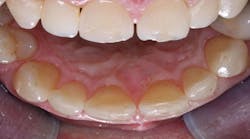

After examining the position, shade, and stability of the hard and soft tissues, we decided to treat the case with a nonprep veneer made from lithium disilicate for tooth 9. For the restoration material, we chose IPS e.max Press HT (Ivoclar) because of its impressive esthetic properties (figure 2). The veneer was produced by dental technician Roberto Della Neve in Naples, Italy.